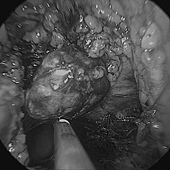

這兩種就比較建議做腎上腺切除手術,但腎上腺很深,傳統上要開一個相當大的傷口才能處理的到,現在因為腹腔鏡的發展,我們只需要打幾個小洞,將器械伸進去處理即可,恢復時間大幅縮短。

💁🏻♂️ 上面這位病人後來查出是腎上腺腫瘤所引發的「原發性高醛固酮症」,就是經由腹腔鏡腎上腺切除後,隔天的電解質立刻回復到正常了,而且目前也不再需要吃降血壓藥了!